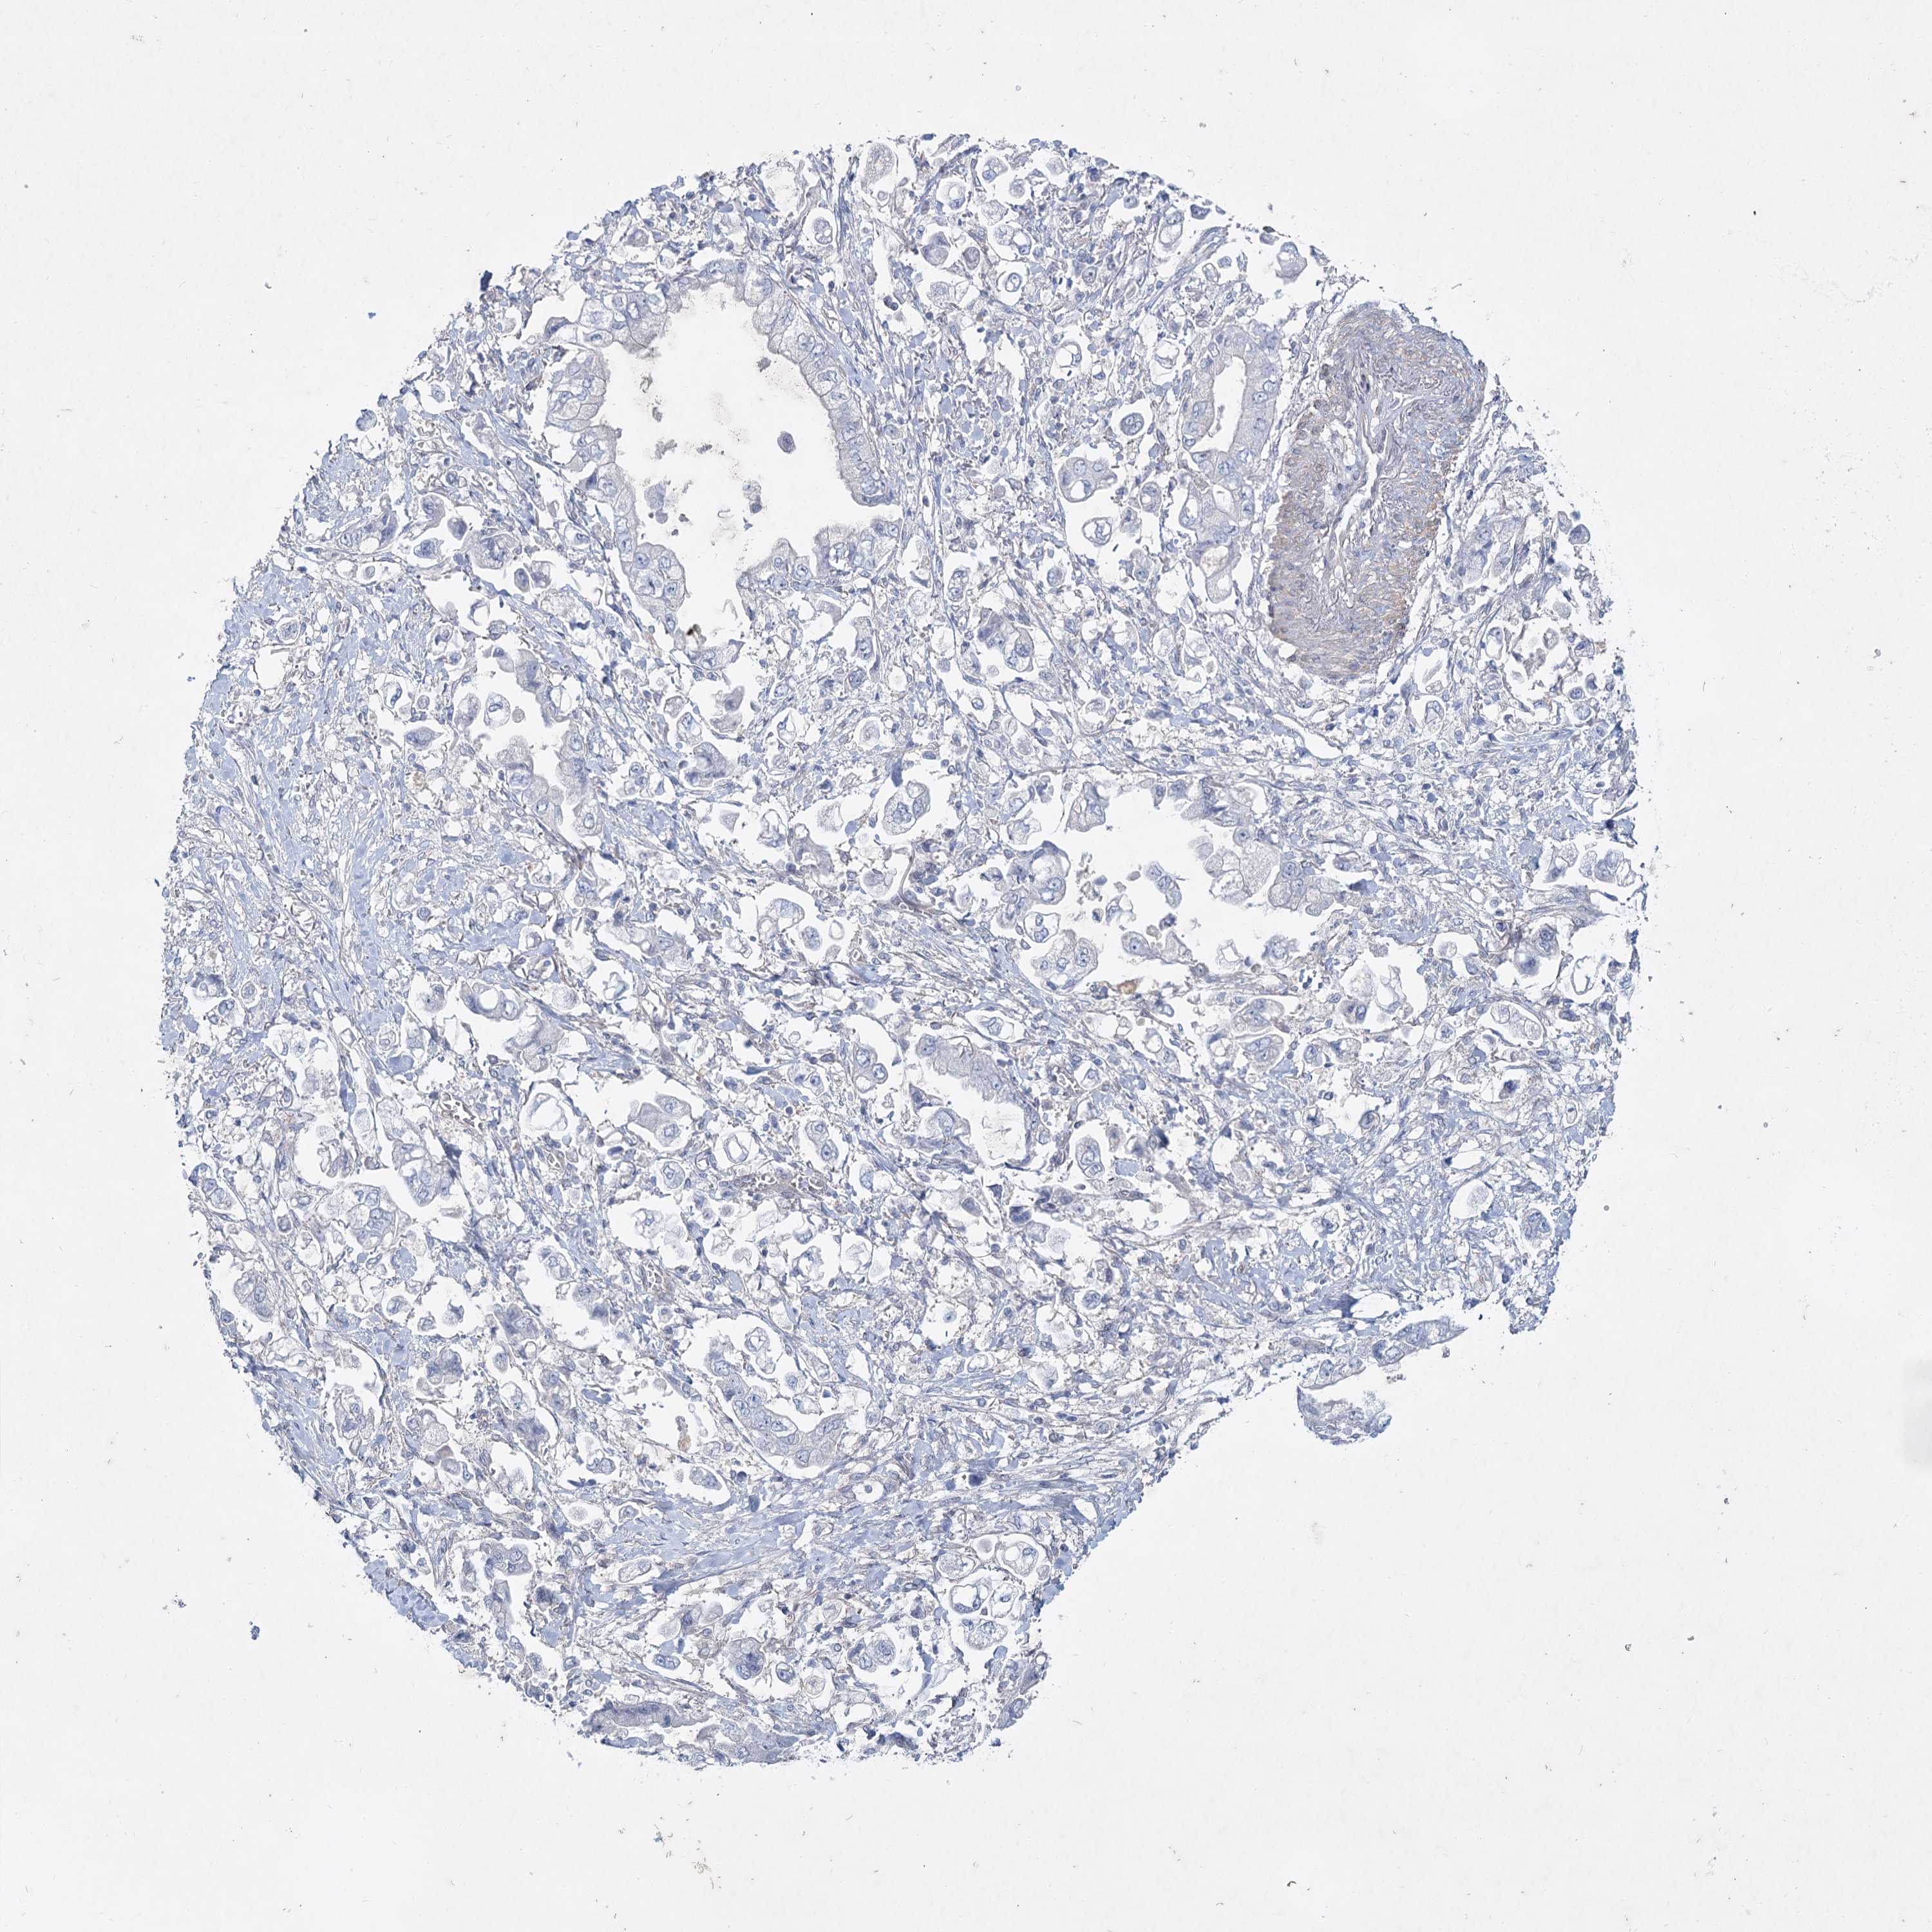

STOMACH CANCER - Protein expressioni

A mouse-over function shows sample information and annotation data. Click on an image to view it in a full screen mode. Samples can be filtered based on level of antibody staining by selecting one or several of the following categories: high, medium, low and not detected. The assay and annotation is described here.

Note that samples used for immunohistochemistry by the Human Protein Atlas do not correspond to samples in the TCGA dataset.

Antibody stainingi

Antibody staining in the annotated cell types in the current human tissue is reported as not detected, low, medium, or high, based on conventional immunohistochemistry profiling in selected tissues. This score is based on the combination of the staining intensity and fraction of stained cells.

Each image is clickable and will lead to virtual microscopy that enables deeper exploration of all samples and also displays staining intensity scores, fraction scores and subcellular localization as well as patient and tissue information for each sample.

Adenocarcinoma, NOS